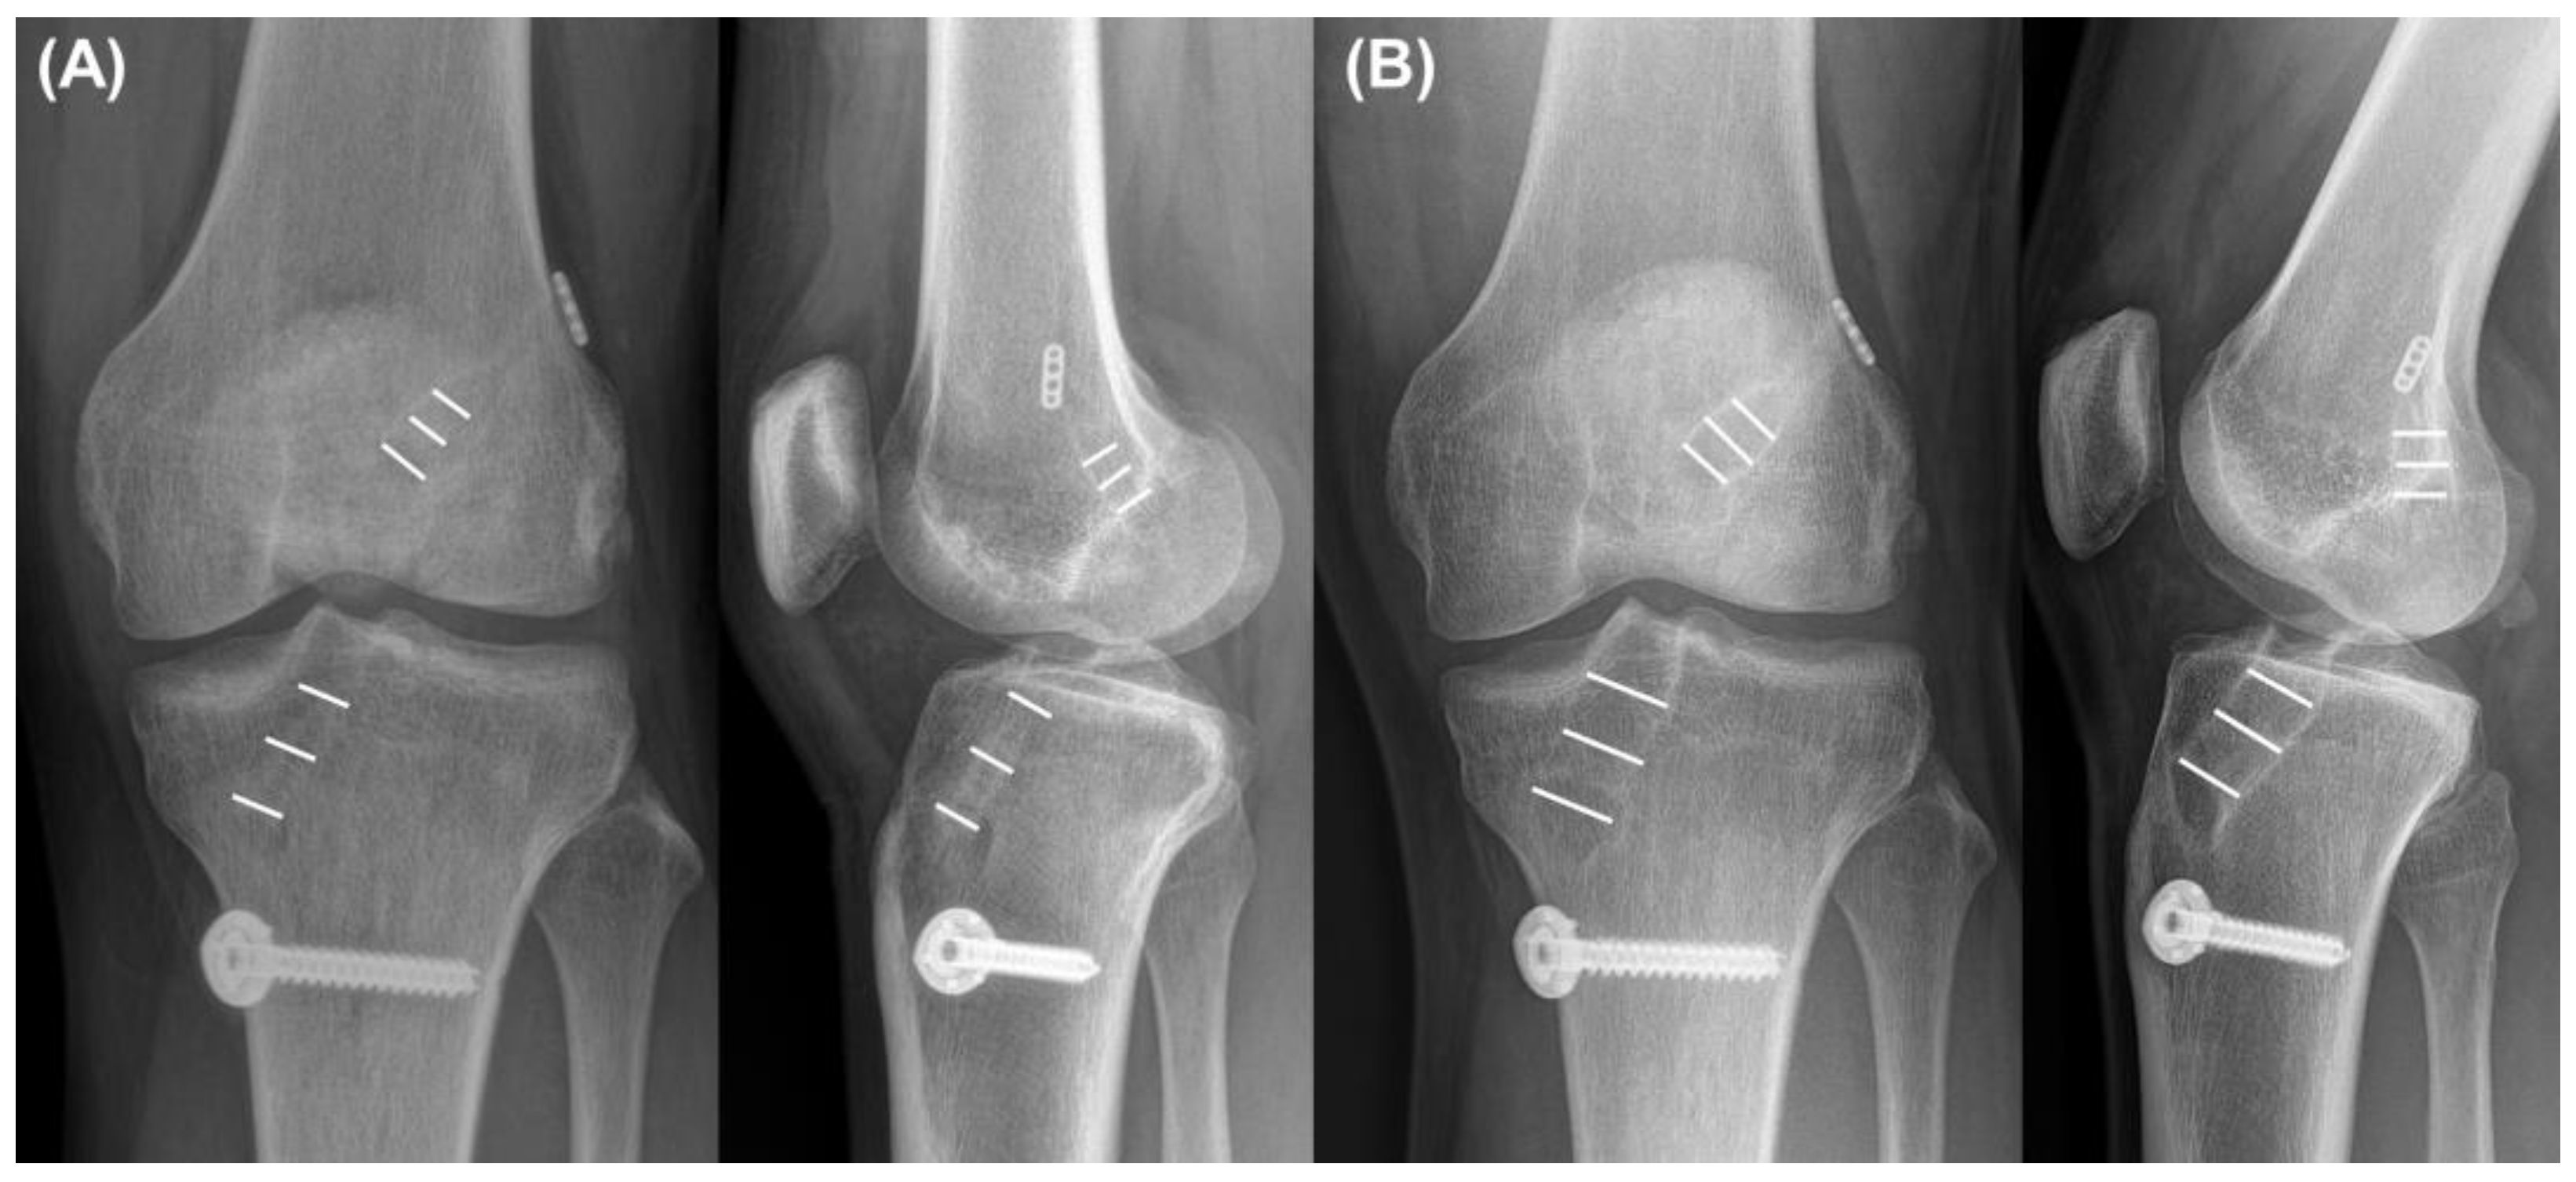

The tunnel widths of the femur and tibia were measured on both knee AP and lateral radiographs, as described in previous reports [28,37]. Immediately and 2 years postoperatively, radiographs were used to measure tunnel widths. The femoral and tibial tunnel widths on the AP (FT-AP and TT-AP, respectively) and lateral views (FT-Lat and TT-Lat, respectively) were measured (Figure 4). The average values of the three different measurement points were used for analysis [9]. Femoral and tibial TWs were defined as the measurement difference between immediate and postoperative results after 2 years on the AP view. The patients were divided into two groups according to femoral and tibial TWs > 3 mm.

Figure 4.

Measurement of (A) immediate and (B) 2-year postoperative tunnel diameters on the anteroposterior and lateral views. Tunnel widths were measured at three points on each tunnel—aperture, midpoint, and exit. Average values of each tunnel were used for analysis.